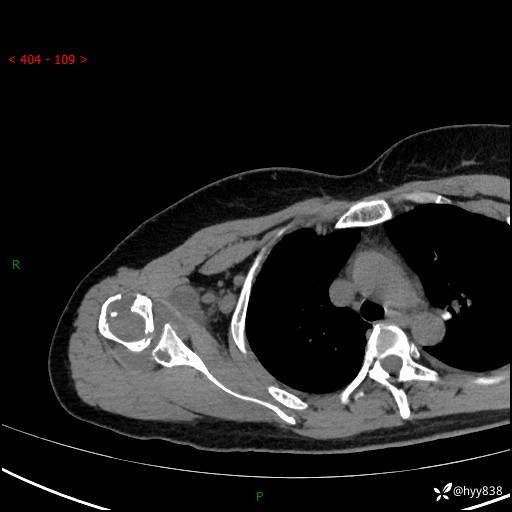

右肩关节平片

右肩关节CT平扫